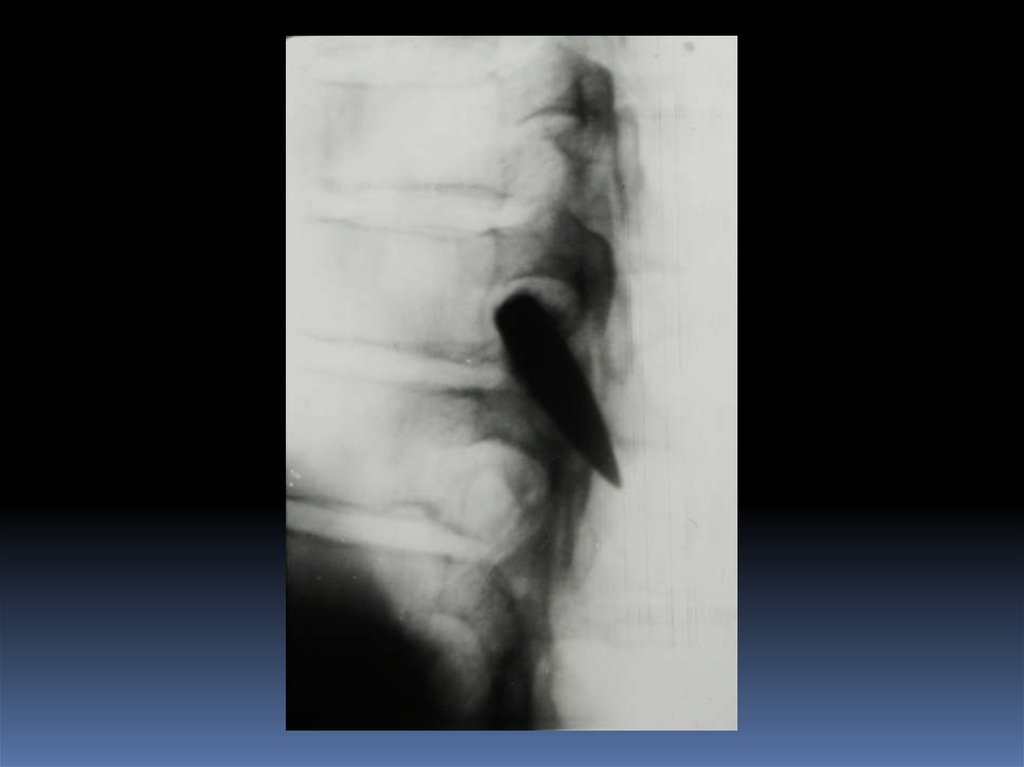

5. Проведение рентгеноскопического исследования раненого.

6. Проведение рентгенографического исследования раненого.

7. Виды травматического повреждения грудной клетки:

пневмоторакс;

гемоторакс;

гемопневмоторакс;

внутрилегочные гематомы;

дисковидные ателектазы;

посттравматические пневмонии.